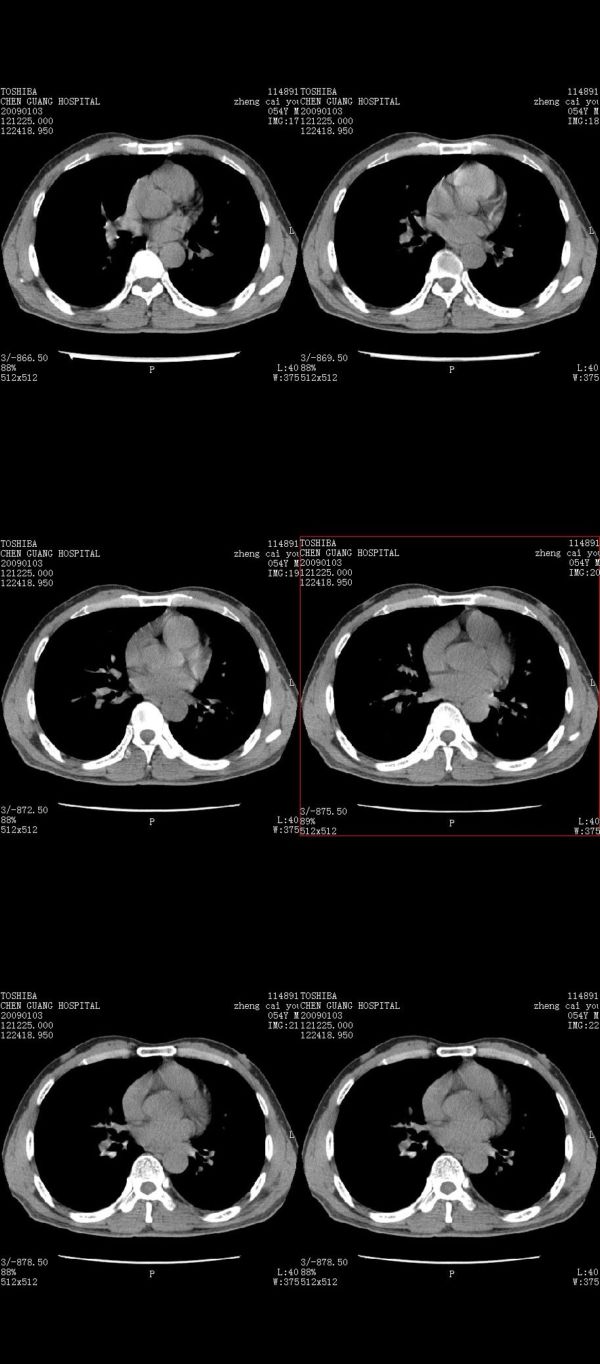

男,54岁,右侧胸部疼痛,平时吸烟,有抽烟后咳嗽咯痰史。昨天没把xiphoid软件吃懂,所以没把纵隔窗图像处理出来!请各位老师帮忙看一下右肺门有没有问题?谢谢!!!!!!!!!!

我同学讲红线部分强化不好,感觉不是很舒服,这是什么道理?

我同学讲红线部分强化不好,感觉不是很舒服,应该 是软组织间隙,不是一个孤立的病灶。

气管前腔静脉后似见增大淋巴结影,肺门区未见明显肿块影。肺窗示右肺中叶外侧段透亮度增高,可过一段时间再查一下对比一下,毕竟是自己的至亲,又有条件,辐射就顾不得了。

也觉得还好吧,只是右下肺动脉显粗了点,纵膈有钙化淋巴结,再有肺窗就更好了

各位老师:奇静脉增宽,肺上未见明显实变,这还需注意观察些什么?????

怎么不发点肺窗,胸痛原因很多,心、血管病变都可能,心、肺血管梗塞等,还包括功能性病变。

右侧肺门影增大,不除外增大淋巴结可能